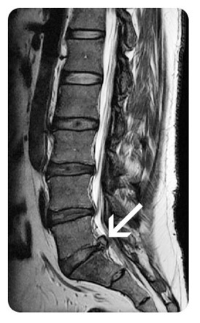

诊断:基于患者的症状、体格检查和影像学结果,张先生被诊断为腰椎间盘突出症。

治疗:患者将接受中医治疗,包括推拿按摩和脊柱牵引,以帮助减轻症状和促进康复。